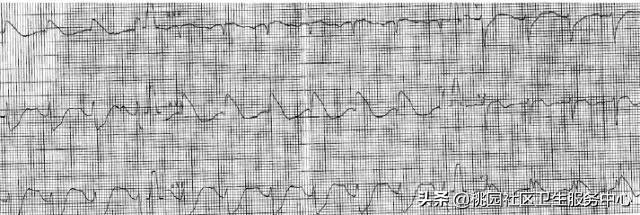

男性,59 岁,胸骨后疼痛伴大汗 8 小时;图 A:发病 1 小时诊:V1~4 的 T 波高尖;图 B:发病 3 小时症状好转:V1~5 ST 段上斜型压低;图 C:发病 8 小时入院:病理性 Q 波形成;图 D:急诊 PCI:LM 斑块,近端狭窄 40%,LAD 近端闭塞,LCX 中段狭窄 70~80%,右冠多发斑块,中段狭窄 70~80%;

1. 急性心肌梗死与右束支传导阻滞(图 A)

根据国内外文献报道,急性心肌梗死合并完全性右束支传导阻滞的发病率在 3%~29%。右束支纤维细且长,位于室间隔右侧表浅的心内膜下。大多数人右束支的血供来自左冠状动脉前降支的第一室间隔支,

AMI 合并完全性右束支传导阻滞时提示存在左冠状动脉前降支近端闭塞,患者多合并严重泵功能障碍,死亡危险性也增高,是前壁心肌梗死预后不良重要危险信号。

2. 急性心肌梗死与左束支传导阻滞(图 B)

急性心肌梗死并完全性左束支传导阻滞发生率约为 2%~4%。左束支位于室间隔左侧的心内膜下, 较右束支粗且分支多、分布广,左束支的血供与右束支亦有不同,右束支与左束支前分支甚接近,位于室间隔的前区,均由冠状动脉左前降支所支配,而左束支主干及左后分支则源于右冠状动脉支配,且后分支系双重血供,即由右冠状动脉及左冠状动脉旋支共同支配,故需有相当程度冠脉病变累及血供源方显示完全性左束支传导阻滞。

左束支一旦发生传导阻滞,将会使心室的电和机械活动顺序发生改变,产生负性的心脏血流动力学效应,引起心力衰竭,对患者预后有较高的预测价值。